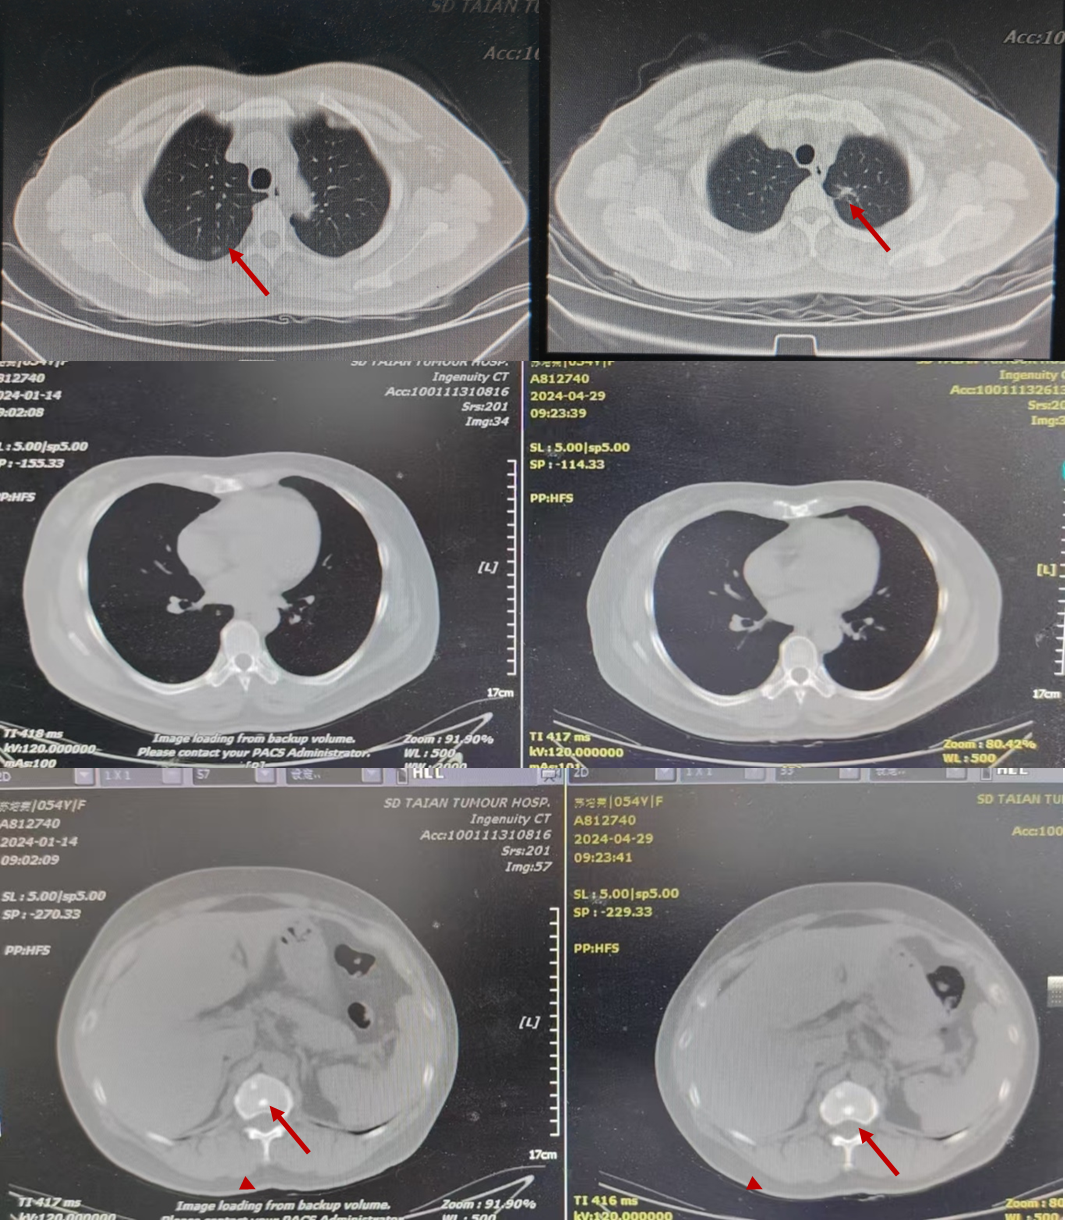

2024年4月29日-2024年6月21日,予“洛拉替尼100mg qd”口服治疗。治疗期间,肝功能及血脂异常,出现恶心、呕吐、腹泻不适,无法耐受,减量后仍无法耐受。患者出现腰痛症状,2024-06-21复查胸部+上腹部CT(图5):左肺原发灶增大,双肺新发转移灶,肝内多发转移灶,部分融合成团;查腰椎+骨盆磁共振(图6):骶尾骨、双侧髂骨、坐骨、耻骨及右侧股骨头、股骨颈骨质信号不均,见多发斑片、结节状异常信号影,T1W1、T2W1呈稍低信号,T2W1脂肪抑制序列呈高信号;子宫左侧壁见类圆形异常信号影,边界尚清,大小约5.6cm×5.7cm,T1W1呈等信号,T2W1呈高低混杂信号;所见盆腔内未见明显肿大淋巴结。

2024-06-21 肝内转移灶穿刺结果示:(肝穿刺)肝组织内查见低分化癌,倾向为转移的肺多形性癌或低分化腺癌。免疫组化:CK(+),CK8/18(+),CK7(-),TTF-1(-),Arginase-1(-),HepPar-1(-),CD31(-),CD34(-),ERG(-),Ki-67阳性率约70%。

2024-06-29 肝转移穿刺基因检测:ALK EML4(13)-ALK(20)突变丰度 2.29%,微卫星稳定MSS,PD-L1表达:0。

疗效评估:PD。

PFS2:近2个月。